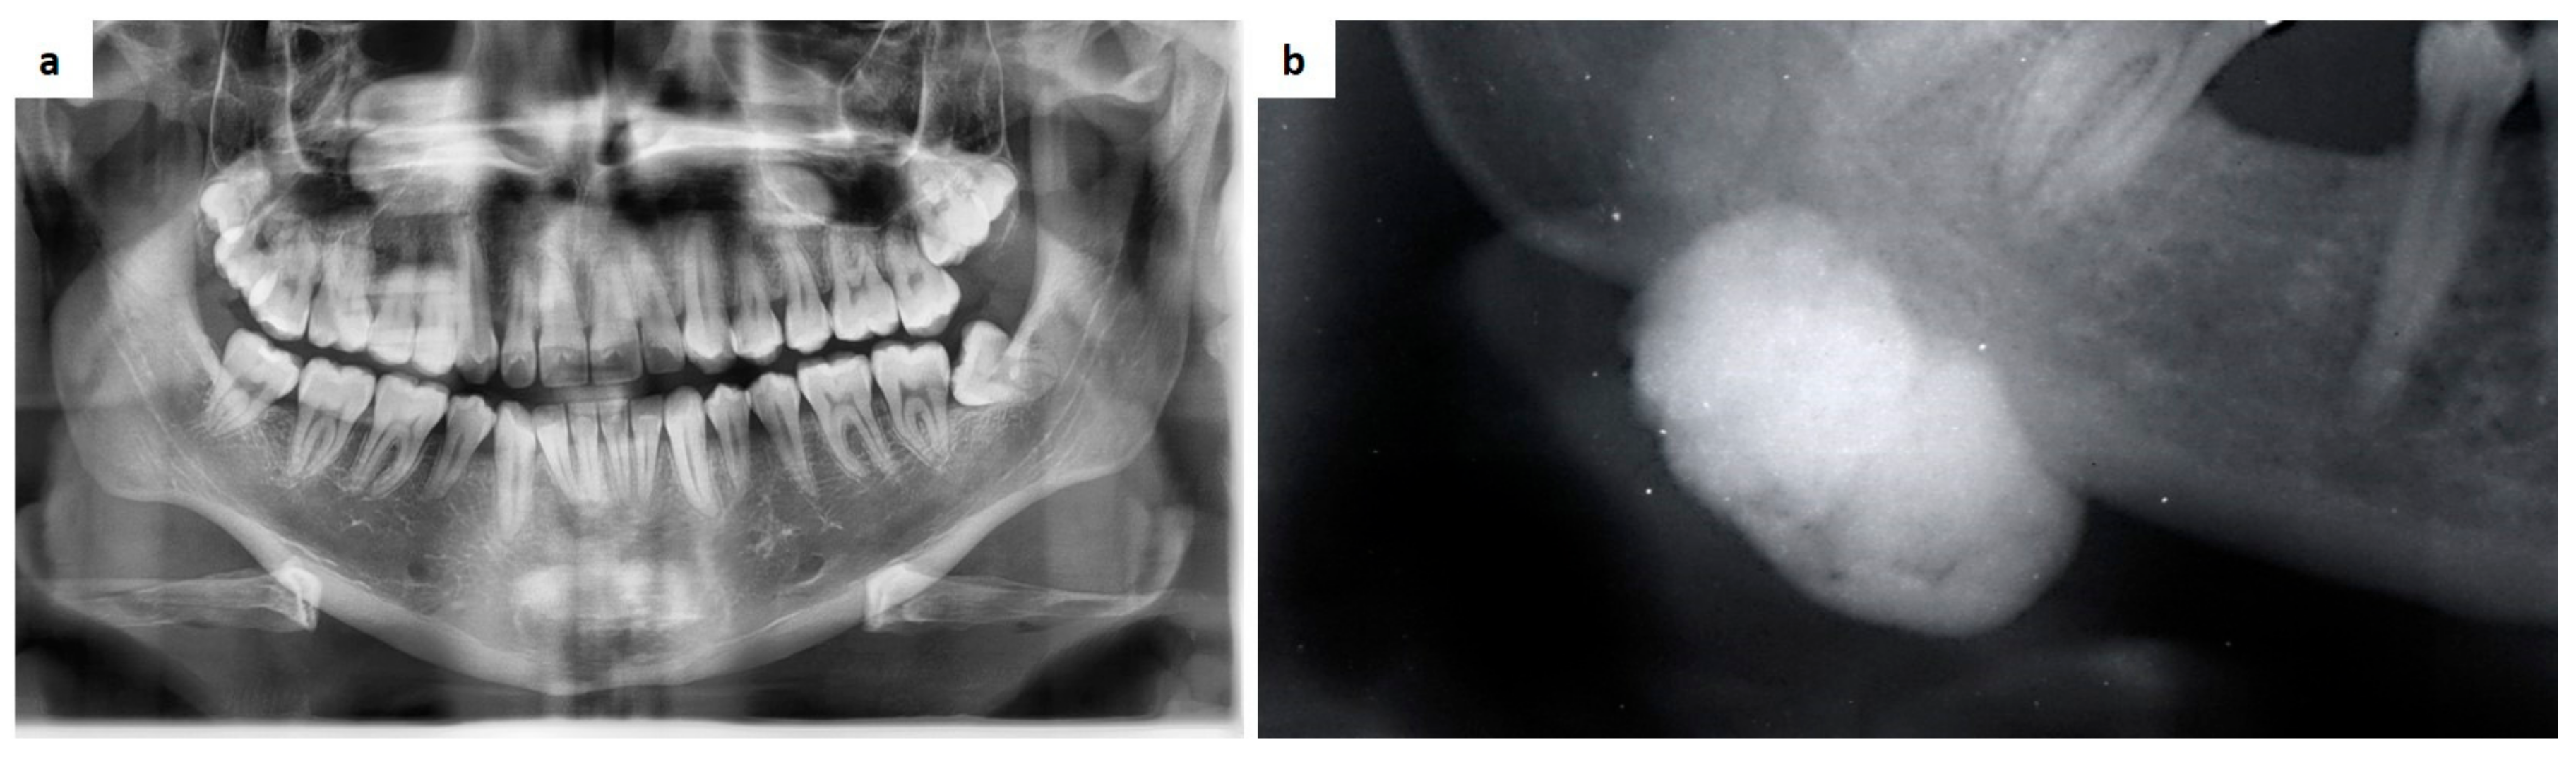

- Capodiferro, S.; Tempesta, A.; Limongelli, L.; Ingravallo, G.; Maiorano, E.; Sfasciotti, G.L.; Bossù, M.; Polimeni, A.; Favia, G. Primary Oro-Facial Manifestations of Langerhans Cell Histiocytosis in Pediatric Age: A Bi-Institutional Retrospective Study on 45 Cases. Children 2020, 7, 104. [Google Scholar] [CrossRef] [PubMed]